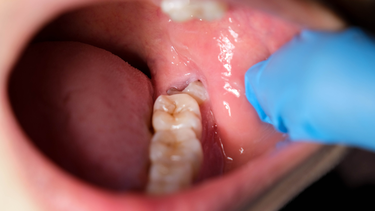

Lợi sưng đỏ, phồng đau

Đây là dấu hiệu dễ nhận thấy nhất khi răng khôn mọc gặp vấn đề. Nướu trùm lên răng có thể sưng đỏ, đau rát khi chạm vào, thậm chí có mủ hoặc dịch chảy ra. Nếu không được chăm sóc và điều trị đúng cách, tình trạng sưng đau sẽ ngày càng nặng hơn, gây khó khăn trong việc ăn nhai và vệ sinh răng miệng.

Viêm lợi trùm răng khôn có mủ

Khi tình trạng viêm tiến triển nặng, trên nướu có thể xuất hiện các đốm mủ trắng kèm theo mùi hôi khó chịu. Đây là dấu hiệu cho thấy vùng lợi đã bị nhiễm trùng sâu, vi khuẩn tích tụ gây tổn thương mô mềm. Lúc này, việc điều trị bằng thuốc thông thường thường không còn hiệu quả, cần có sự can thiệp của bác sĩ chuyên khoa để làm sạch và dẫn lưu mủ đúng cách.